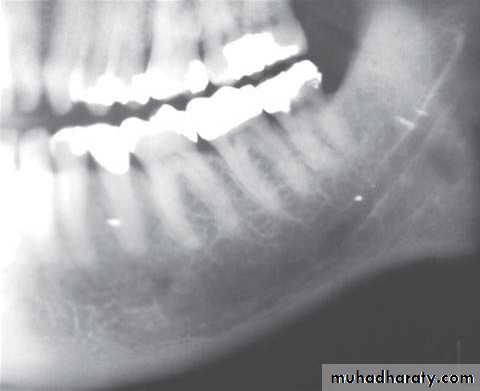

Location: posterior body of the mandible.

Periphery: ill defined with gradual transition to normal trabeculae.

Internal structure: *Decrease in bone density.

* Loss of trabecular sharpness.

*Scattered areas of radiolucency.

* Sclerotic regions → sequestra.

Effect on surrounding structures:

*Bone resorption or bone formation.*Bone formation is parallel to bone surface and lift the periosteum.

*A radiolucent band separates this periosteal new

bone from the bone surface.

This is continue to form several radiopaque lines

separated by radiolucent bands (Onion-skin

appearance) → Proliferative periostitis